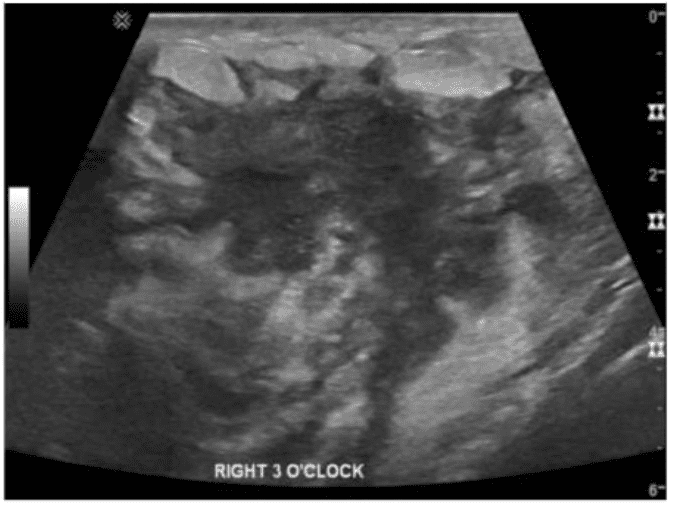

Which condition is demonstrated in this image of a febrile patient with breast redness and tenderness?